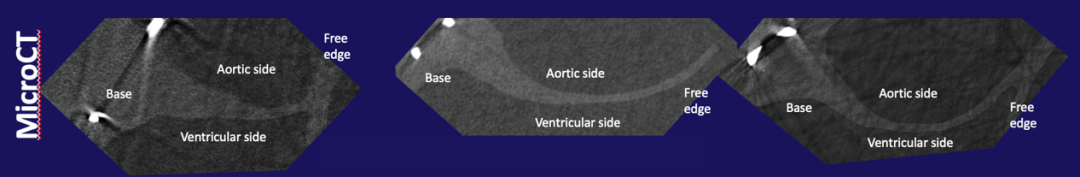

诊断亚临床瓣叶血栓形成的金标准是四维计算机断层扫描(4DCT),其特征性发现是瓣叶基底部低密度影或低衰减瓣叶增厚。HALT可潜在影响瓣膜功能和临床结局,因此由心脏CT确认HALT可能对改善经导管主动脉瓣膜(TAV)的长期耐久性非常重要。而更高分辨率成像手段,如microCT,可以进一步深入了解HALT的病理生理学和区分HALT的不同阶段。

2)比较HALT的microCT特征与急性期、机化期和机化血栓形成的组织学表现(microCT分辨率为微米,临床CT分辨率为0.5mm)。

通过MicroCT和组织学分别评估瓣叶增厚程度。在110例TAV中,40例进行了microCT图像采集。在排除4例(3例严重固有钙化;1例图像质量差)之后,36例可用于microCT分析。microCT上的HALT定义为瓣叶厚度增加(>正常),并根据瓣叶受累长度进行分级(肉眼评估)。组织学测定瓣叶增厚的成分,并与MicroCT进行比较。

但microCT却不能具体区分血栓类型。

组织学分析证实了血栓的3种类型:急性血栓、机化期血栓和机化血栓,而通过microCT无法区分血栓的具体类型。植入时间超过30天的瓣膜组织学特征与机化一致,而大多数植入时间超过1年的瓣膜血栓为机化期或机化血栓。